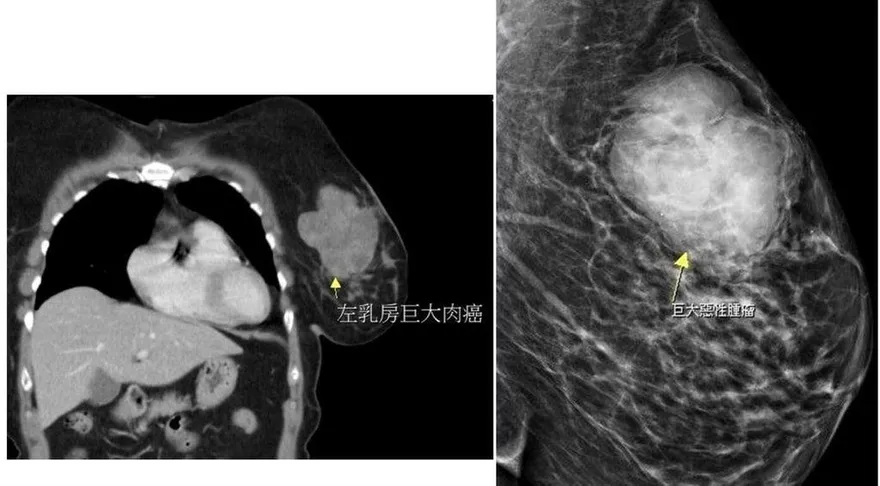

乳腺癌

乳癌

肉癌